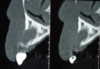

ガイド使用フラップレス骨移植インプラント同時症例

通常これほど骨が薄い場合は上の症例の様な大きな骨の移植が必要となりますが、シュミレーションソフトを使い審査したところギリギリでインプラント埋入と同時に骨の移植を行えると判断。

またシュミレーションを基に作成したインプラント手術ガイドを使用したので歯茎を切らないフラップレスで手術を行うことができました。

フラップレス手術はよくありますが実際は精度が悪くなり術後の歯茎の退縮も起こりやすいので状態が良くないと行わないですが、痛みも少なく患者さんに優しい方法です。

また骨の移植もインプラント埋入の為に開けた穴から空洞内の粘膜を剥がしスペースに移植する方法でこちらも難度が高く半数以上の症例で失敗している(少しの失敗では一部インプラントと結合するので失敗の及ぼす影響はわかりにくいです)という統計データも存在しますが、こちらも術後の痛みも少なく治療期間も大きな移植と比較して6か月程度短縮することができます。

当院では術後にCT撮影を行い結果をごまかさずに患者さんと一緒に確認しています。